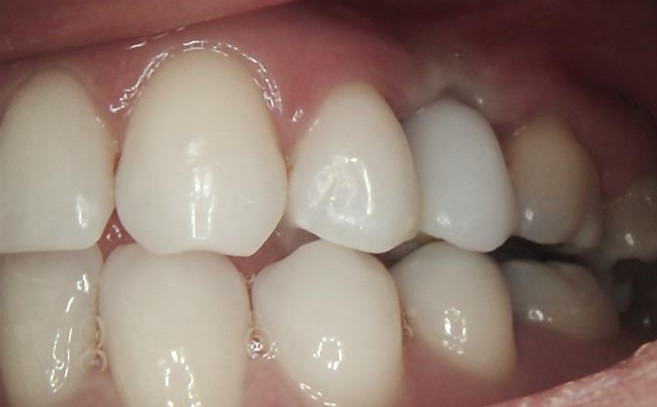

FINAL

After successful osseointegration, the definitive restoration was delivered using a Ti-base-supported crown, held by Dr Carmy.

Final radiographic evaluation confirmed proper implant positioning and bone stability.

The treatment resulted in a functional, stable, and esthetically harmonious restoration fully integrated with the adjacent dentition.